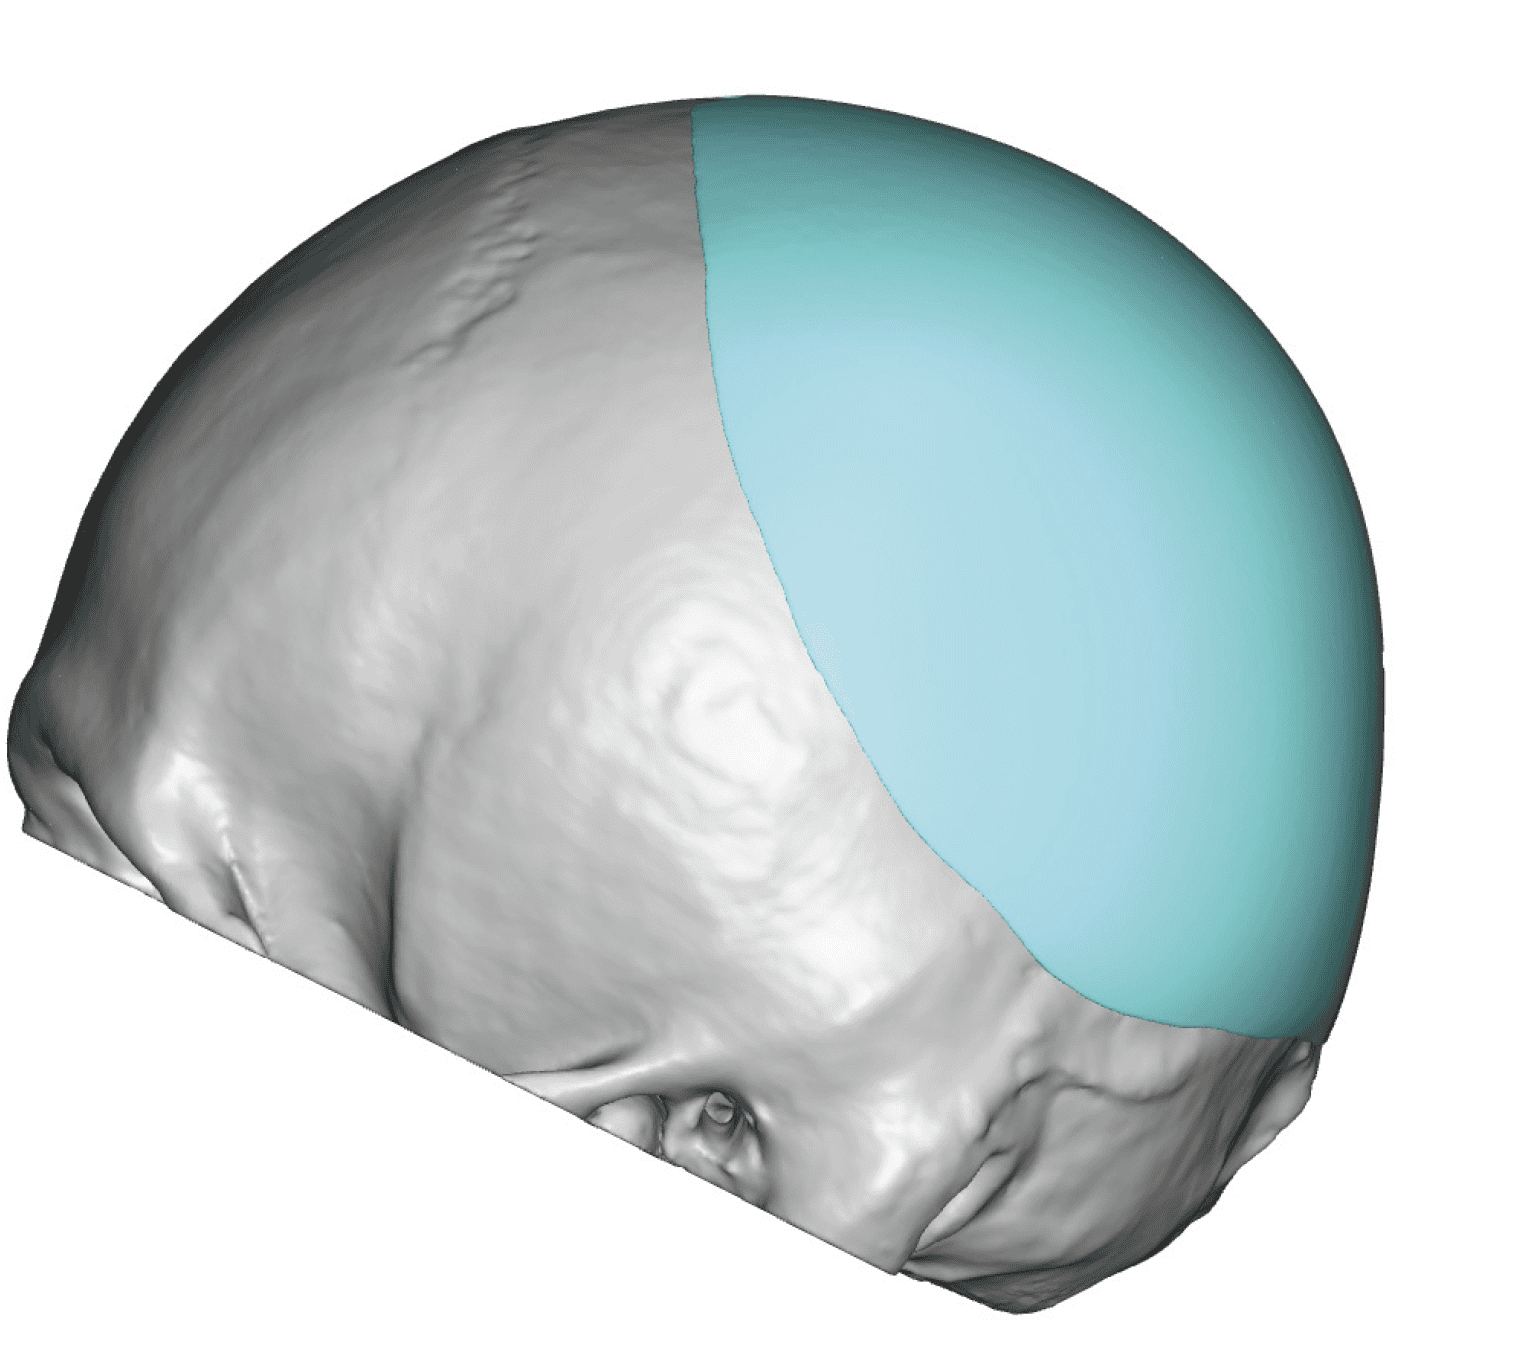

Severe narrowing skull deformity from prior sagittal craniosynostosis repair as an adult.

Complete replacement of entire skull by a custom implant with temporal fat injections.

Severe narrowing skull deformity from prior sagittal craniosynostosis repair as an adult.

Complete replacement of entire skull by a custom implant with temporal fat injections.